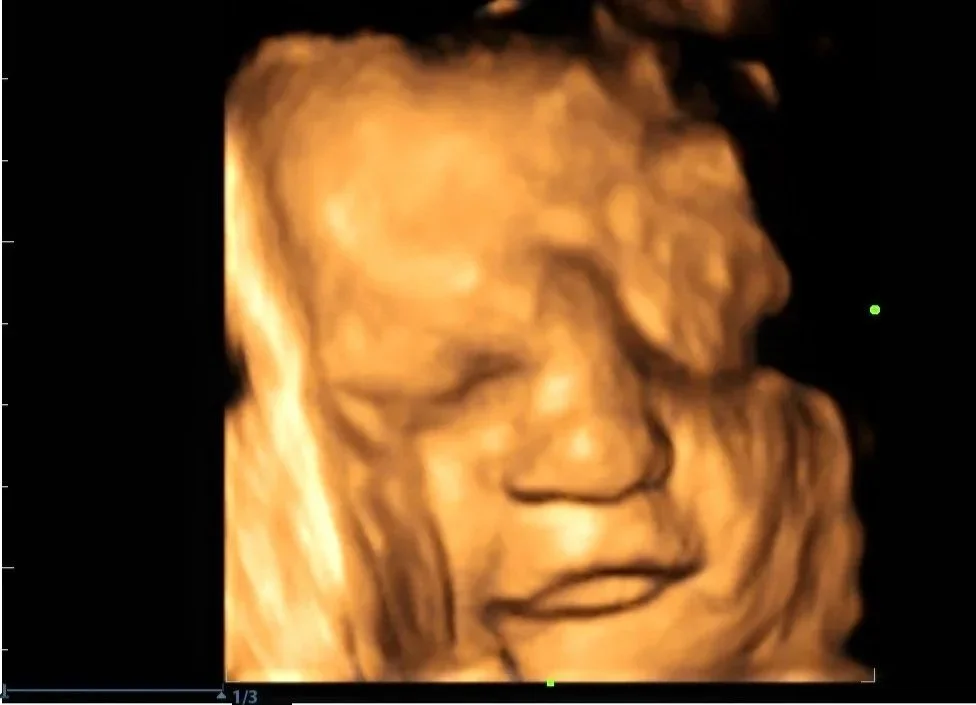

The Signature 3D

A breathtaking view of your baby’s face, yawns, stretches, and little movements — a keepsake to treasure forever.

• 25–30 minute 3D/4D ultrasound